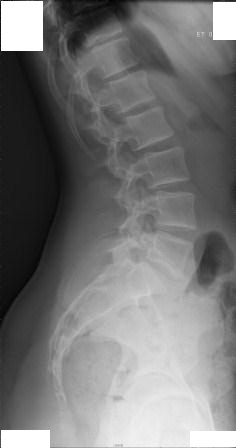

Hier sind alle Röntgenbilder.

Ist es jetzt anhand diesen Bildern nötig, zu einem Osteopathen zu gehen oder nicht?

- seitenansicht 1.jpg (16.39 KiB) 7115 mal betrachtet

- seitenansicht 2.jpg (12.07 KiB) 7115 mal betrachtet

Es ist in jedem Fall erforderlich !

Gerade bei einer 13-jährigen !

Ein Hohlkreuz ist zu sehen, der Rundrücken ist aufgrund der fehlenden Seitenansicht 3 nicht richtig einzuschätzen.

Die Skoliose im LWS Bereich (ich kann den Grad nicht abschätzen, oberer Bereich fehlt) sollte auf jeden Fall angegangen werden.

Ich habe den COB Winkel Lumbal ausgemessen, allerdings nur auf dem Bildschirm und komme auf ca 9° Lumbal. Eine deutliche Rotation erkenne ich nicht.

Auf dem frontalen RTG Bild ist zu sehen, dass das Becken nicht ganz gerade ist. Somit ist es möglich, dass Linkes Bein etwas kürzer ist als das Rechte und somit eine Statische Skoliose vorliegt, da die Statische Skoliose in Richtung des Verkürzten Beines geht und das ist auch hier der fall, die Verkrümmung Lumbal geht nach links.

Es währe sicher sinnvoll deine Schwester einem Orthopäden vorzustellen und bei der nächsten RTG Kontrolle, falls nötig die Beinlänge Ausgleichen.